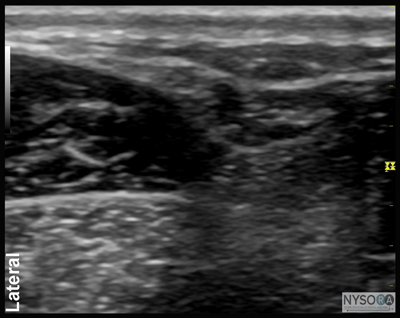

Figure 13: (A) Ultrasound anatomy of the sural nerve (SuN). The SuN is seen immediately anterior to the small saphenous vein (SSV). (B) The ultrasound anatomy of the SuN with the structures labeled. SoM, soleus muscle. ![]() Figure 14: Transducer position and needle position to block the saphenous nerve. Equipment Equipment needed includes the following:

Figure 7:Transducer position and needle insertion to block the superficial peroneal nerve. ![]() Figure 8: Cross-sectional anatomy of the superficial peroneal nerve (SPN). EDL, extensor digitorum longus muscle; PBM, peroneus brevis muscle. Superficial Peroneal Nerve The superficial peroneal nerve innervates the dorsum of the foot. It emerges to lie superficial to the fascia 10 to 20 cm above the ankle joint on the anterolateral surface of the leg. A transducer placed transversely on the leg, approximately 5 cm proximal and anterior to the lateral malleolus, will identify the hyperechoic nerve lying in the subcutaneous tissue immediately superficial to the fascia (Figures 7, 8, and 9A and B). If the nerve is not readily apparent, the transducer can be traced proximally on the leg until, at the lateral aspect, the extensor digitorum longus and peroneus longus muscles can be seen with a prominent groove between them leading to the fibula (Figure 10A and B). The superficial peroneal nerve is located in this intermuscular septum, just deep to the fascia. Once it is identified at this more proximal location, it can be traced distally to the ankle. Because the superficial nerves are rather small, their identification with ultrasound is not always possible in a busy clinical environment. Sural Nerve The sural nerve innervates the lateral margin of the foot and ankle. Proximal to the lateral malleolus, the sural nerve can be visualized as a small hyperechoic structure that is intimately associated with the small saphenous vein (Figures 11, 12, and 13A, B). A calf tourniquet can be used to increase the size of the vein, aiding in identification of the nerve. Saphenous Nerve The saphenous nerve innervates the medial malleolus and a variable portion of the medial aspect of the leg below the knee. The nerve travels down the medial leg alongside the saphenous vein. Because it is a small nerve, it is best visualized 10-15 cm proximal to the medial malleolus, using the saphenous vein as a landmark (Figures 14, 15, and 16A, B). A proximal calf tourniquet can be used to assist in increasing the size of the vein. The nerve appears as a small hyperechoic structure.